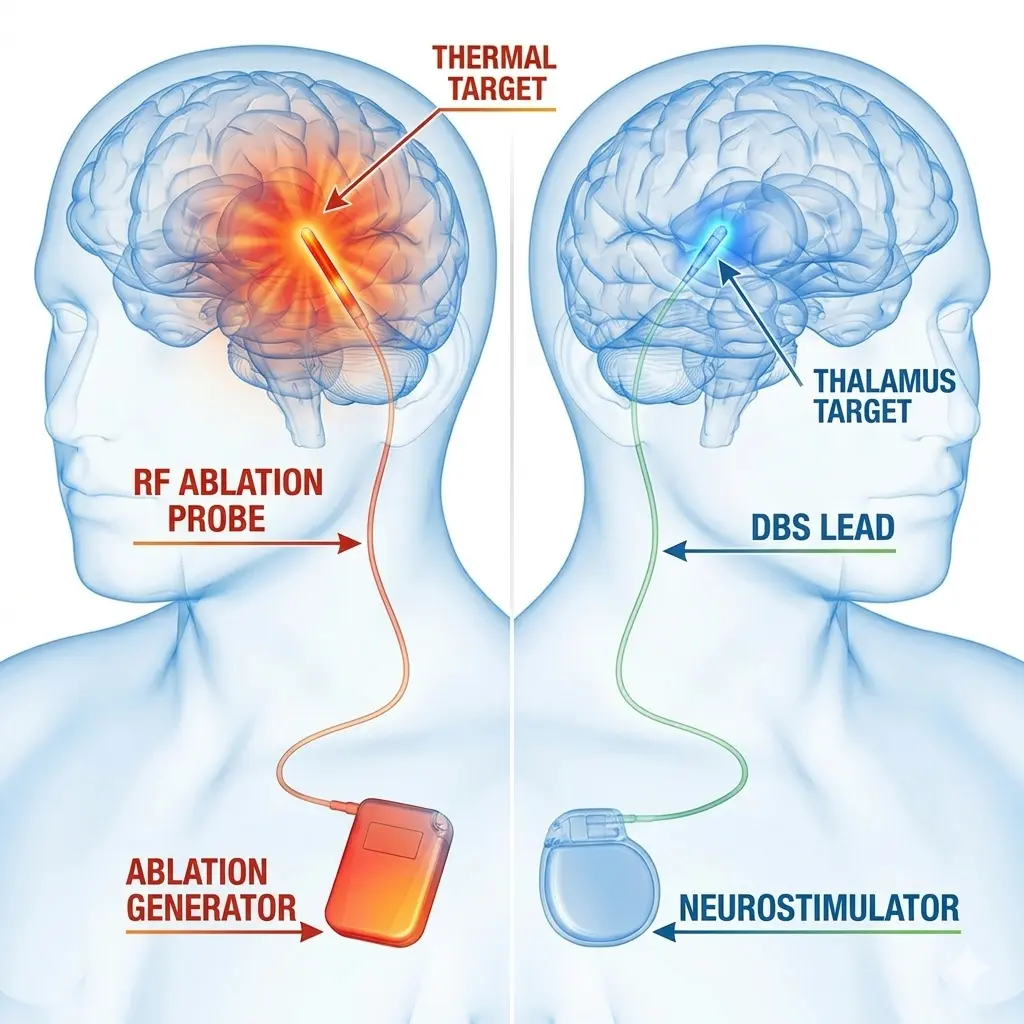

As a specialist in Functional Neuromodulation Surgery, he offers advanced treatments including Deep Brain Stimulation (DBS) for Parkinson’s disease, epilepsy surgery, and procedures for chronic neurological conditions. He is among the first neurosurgeons in Gujarat to develop expertise in this highly specialized field.

Pioneer of Functional Neuromodulation Surgery in Gujarat

As one of the first neurosurgeons in Gujarat to specialize in Functional Neuromodulation Surgery, Dr. Solanki has introduced advanced treatments such as Deep Brain Stimulation (DBS), epilepsy surgery, and procedures for movement disorders and chronic pain.